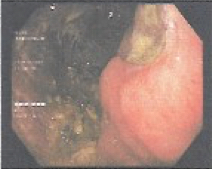

Gastric abnormalities show nonspecific gastrointestinal symptoms and similarly radiological findings. Intra and extra luminal gastric wall thickening are the most common finding in benign and malignant pathologic process. This aim of this case report was to describe several characteristics such as the location and size of the lesion, involvement of the gastric wall and surrounding structures, calcifications, and contrast enhancement pattern which can assist in radiological diagnosis. Several cases at our institution have similar gastrointestinal complaints, however, there were different lesions characteristic found in contrast enhanced abdominal CT scan. The first case 72-years-old man experienced hematemesis with radiologic finding diffuse gastric mucosal thickening as well as homogenous contrast enhancement but without calcification. The second case 37-years-old man complaint dizziness and melena with radiologic finding large tumor more than 10 cm in size, amorph calcification and heterogenous contrast enhancement. The last 60-years-old man case experienced melena and hematemesis, from abdominal CT scan showed irregular gastric mucosal thickening with heterogenous contrast enhancement and fat stranding around the lesion, without calcification. Methods used in these cases were contrast-enhanced abdominal CT scan, esophagogastroduodenoscopy (EGD), and biopsy in order to determine the diagnosis. Contrast-enhanced abdominal CT scan plays a vital role in describing the lesion characteristics which affects the determination of treatment options and future prognosis.